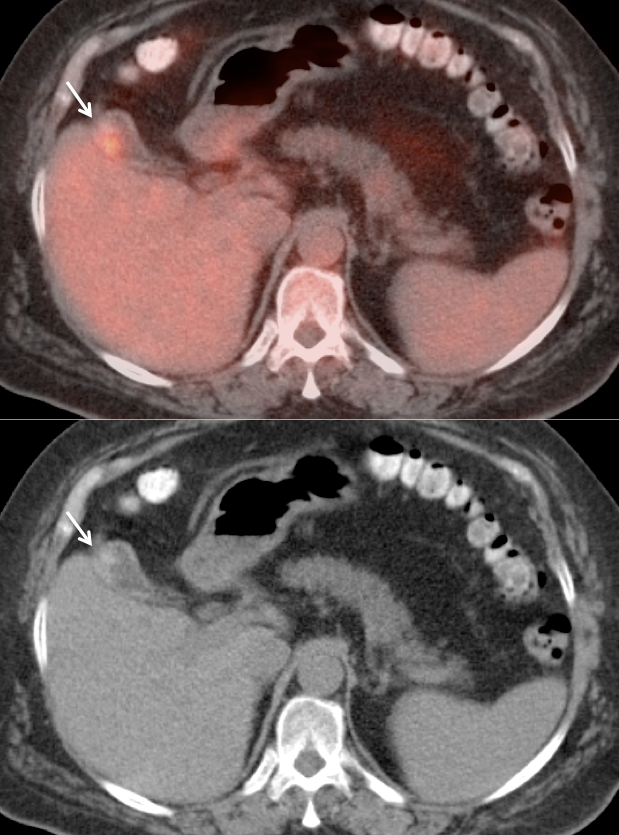

- While PET/CT can detect the primary lesion, its true utility lies in the detection of regional nodes and distant metastatic disease.

- Distant Disease: Most commonly to the liver, lung and brain.

Assessing Response to Therapy & Prognosis:

- Early Response: Non-responders can be offered alternative therapy.

- Late Response: Assess success or failure of therapy, and ultimate outcome.